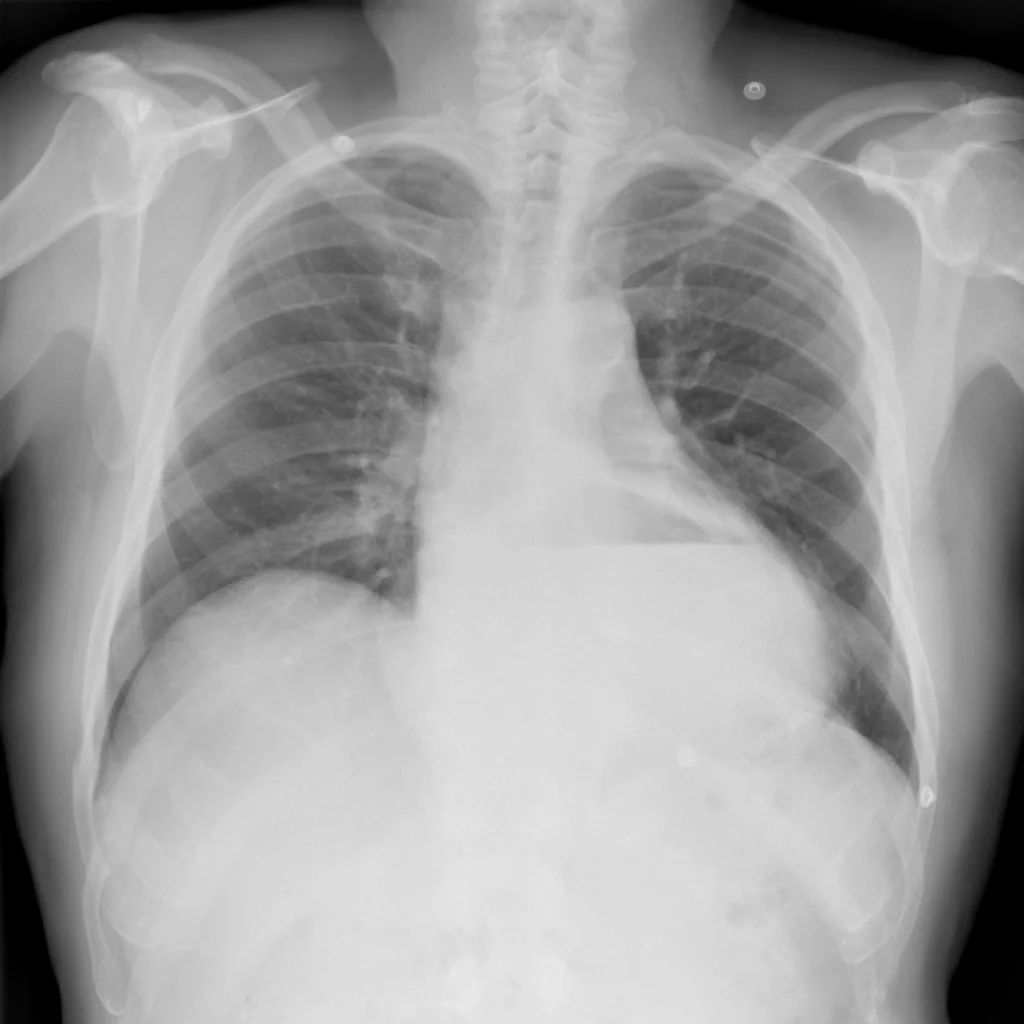

Radiología

Rx de tórax PA. Se observa un nivel hidroaéreo superpuesto a la silueta cardiaca y ausencia de imagen del techo gástrico en proyección subfrénica izquierda, imagen sugestiva de hernia hiatal.